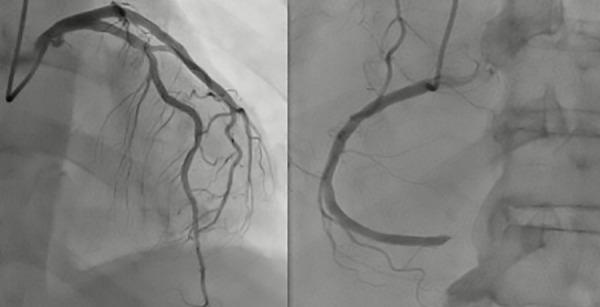

Coronary embolism (CE) is a rare cause of non-atherosclerotic acute coronary syndrome (ACS). The clinical presentation is similar to ACS, and the diagnosis is supported by Shibata criteria. Atrial fibrillation is the main reported etiology in CE cases. Management includes percutaneous intervention with thromboaspiration and anticoagulation. The following case is a description of a patient with acute chest pain and recently diagnosed atrial fibrillation (AF) with a rapid ventricular response, is described. A thrombotic lesion in the distal right coronary artery (RCA) of embolic origin, was documented. Successful mechanical thromboaspiration was performed; intravascular ultrasound (IVUS) showed no thrombus, dissection, or atherosclerotic plaque. CE is an underdiagnosed cause of ACS; diagnosis relies on Shibata criteria, and patients experience worse outcomes in follow-up.

摘要

冠状动脉栓塞(CE)是引起非动脉粥样硬化性急性冠状动脉综合征(ACS)的罕见原因。其临床表现与ACS相似,Shibata标准有助于诊断。心房颤动是CE病例中主要的报告病因。治疗包括经皮血栓抽吸介入治疗和抗凝治疗。以下病例描述了一名患有急性胸痛且近期诊断为心房颤动(AF)伴快速心室反应的患者。记录显示右冠状动脉(RCA)远端存在栓塞性血栓病变。成功进行了机械血栓抽吸;血管内超声(IVUS)显示无血栓、夹层或动脉粥样硬化斑块。CE是ACS的一个诊断不足的病因;诊断依赖于Shibata标准,且患者在随访中预后较差。